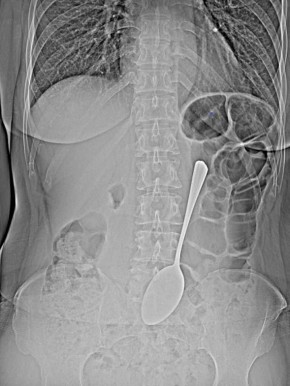

ну вот какВрачи-эндоскописты БСМП им.В.В.Ангапова спасли женщину, которая проглотила столовую ложку.Предмет достали из желудка с помощью эндоскопа и соответствующих инструментов, что помогло избежать сложной хирургической операции...

В Улан-Удэ врачи БСМП имени Ангапова оказали помощь пациентке, проглотившей столовую ложку. Медики извлекли металлический предмет из желудка с помощью эндоскопического оборудования, что позволило...

Врачи-эндоскописты БСМП им.В.В.Ангапова извлекли из желудка обычной женщины обычную столовую ложку. Предмет достали из желудка с помощью эндоскопа и соответствующих инструментов, что помогло избежать сложной хирургической операции.- Инородные предметы...

Ложку врачи-эндоскописты БСМП сумели достать из желудка с помощью эндоскопа и соответствующих инструментов. Так что женщина избежала сложной хирургической операции